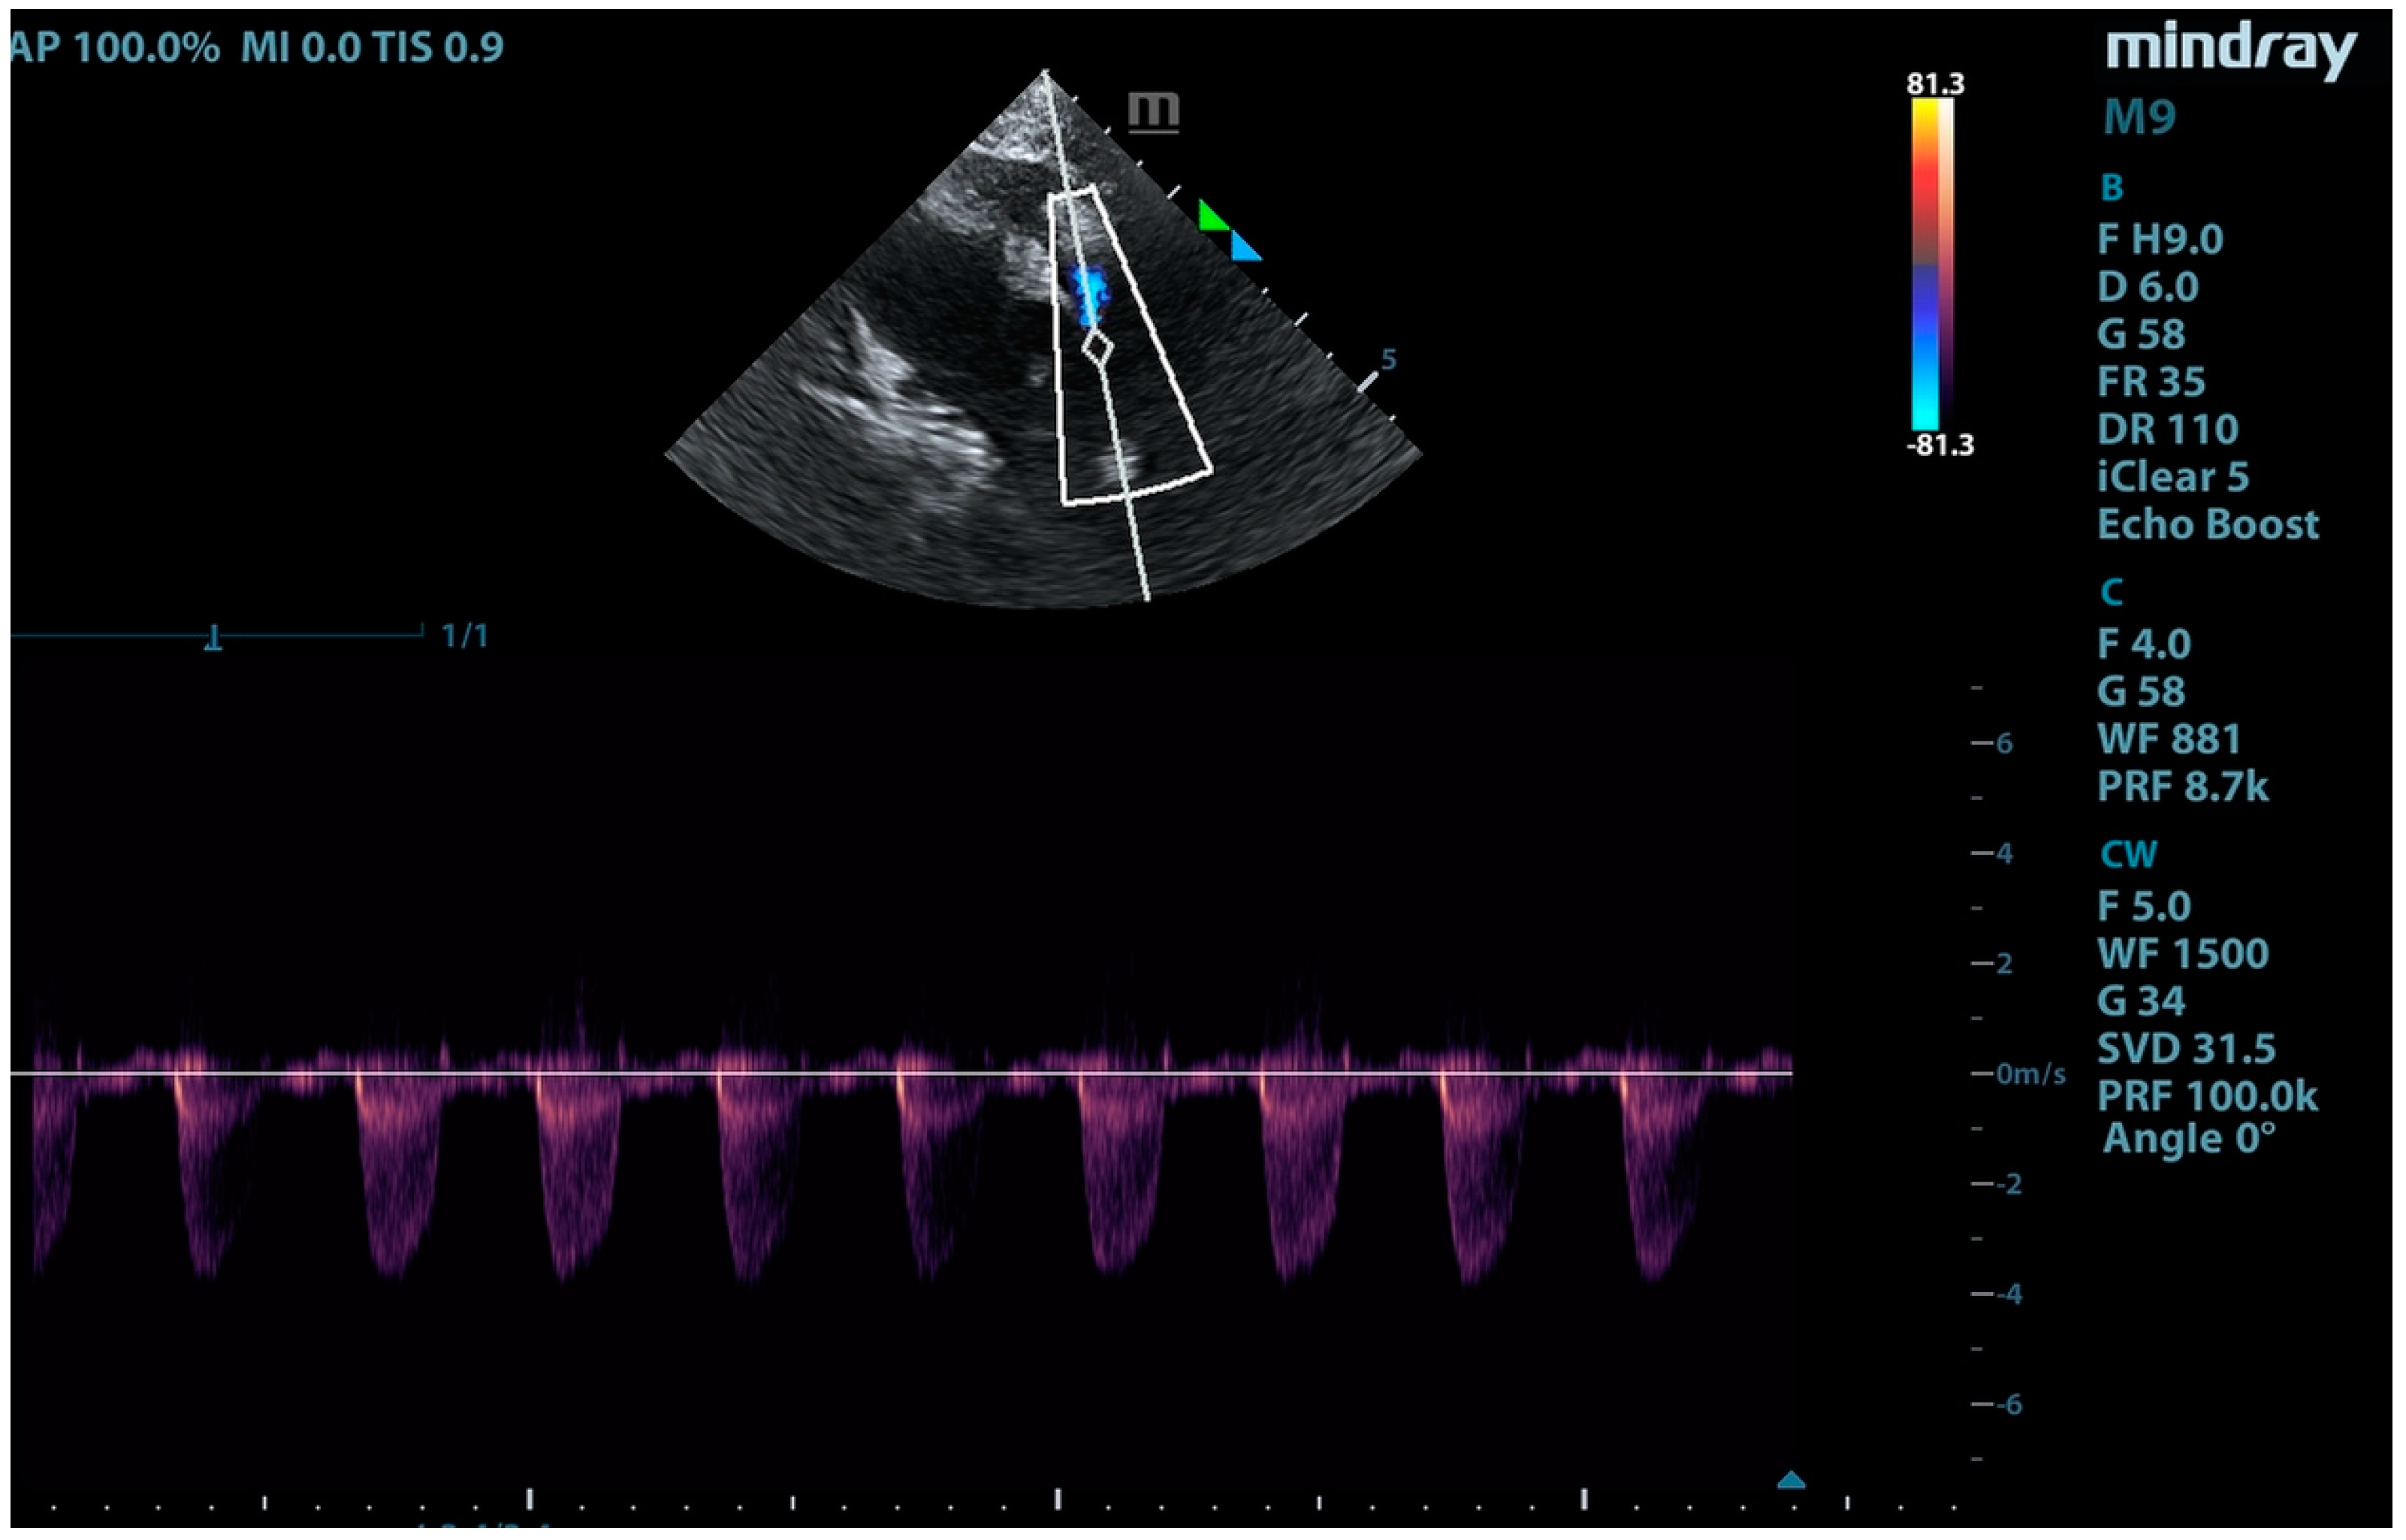

2. Case Presentation